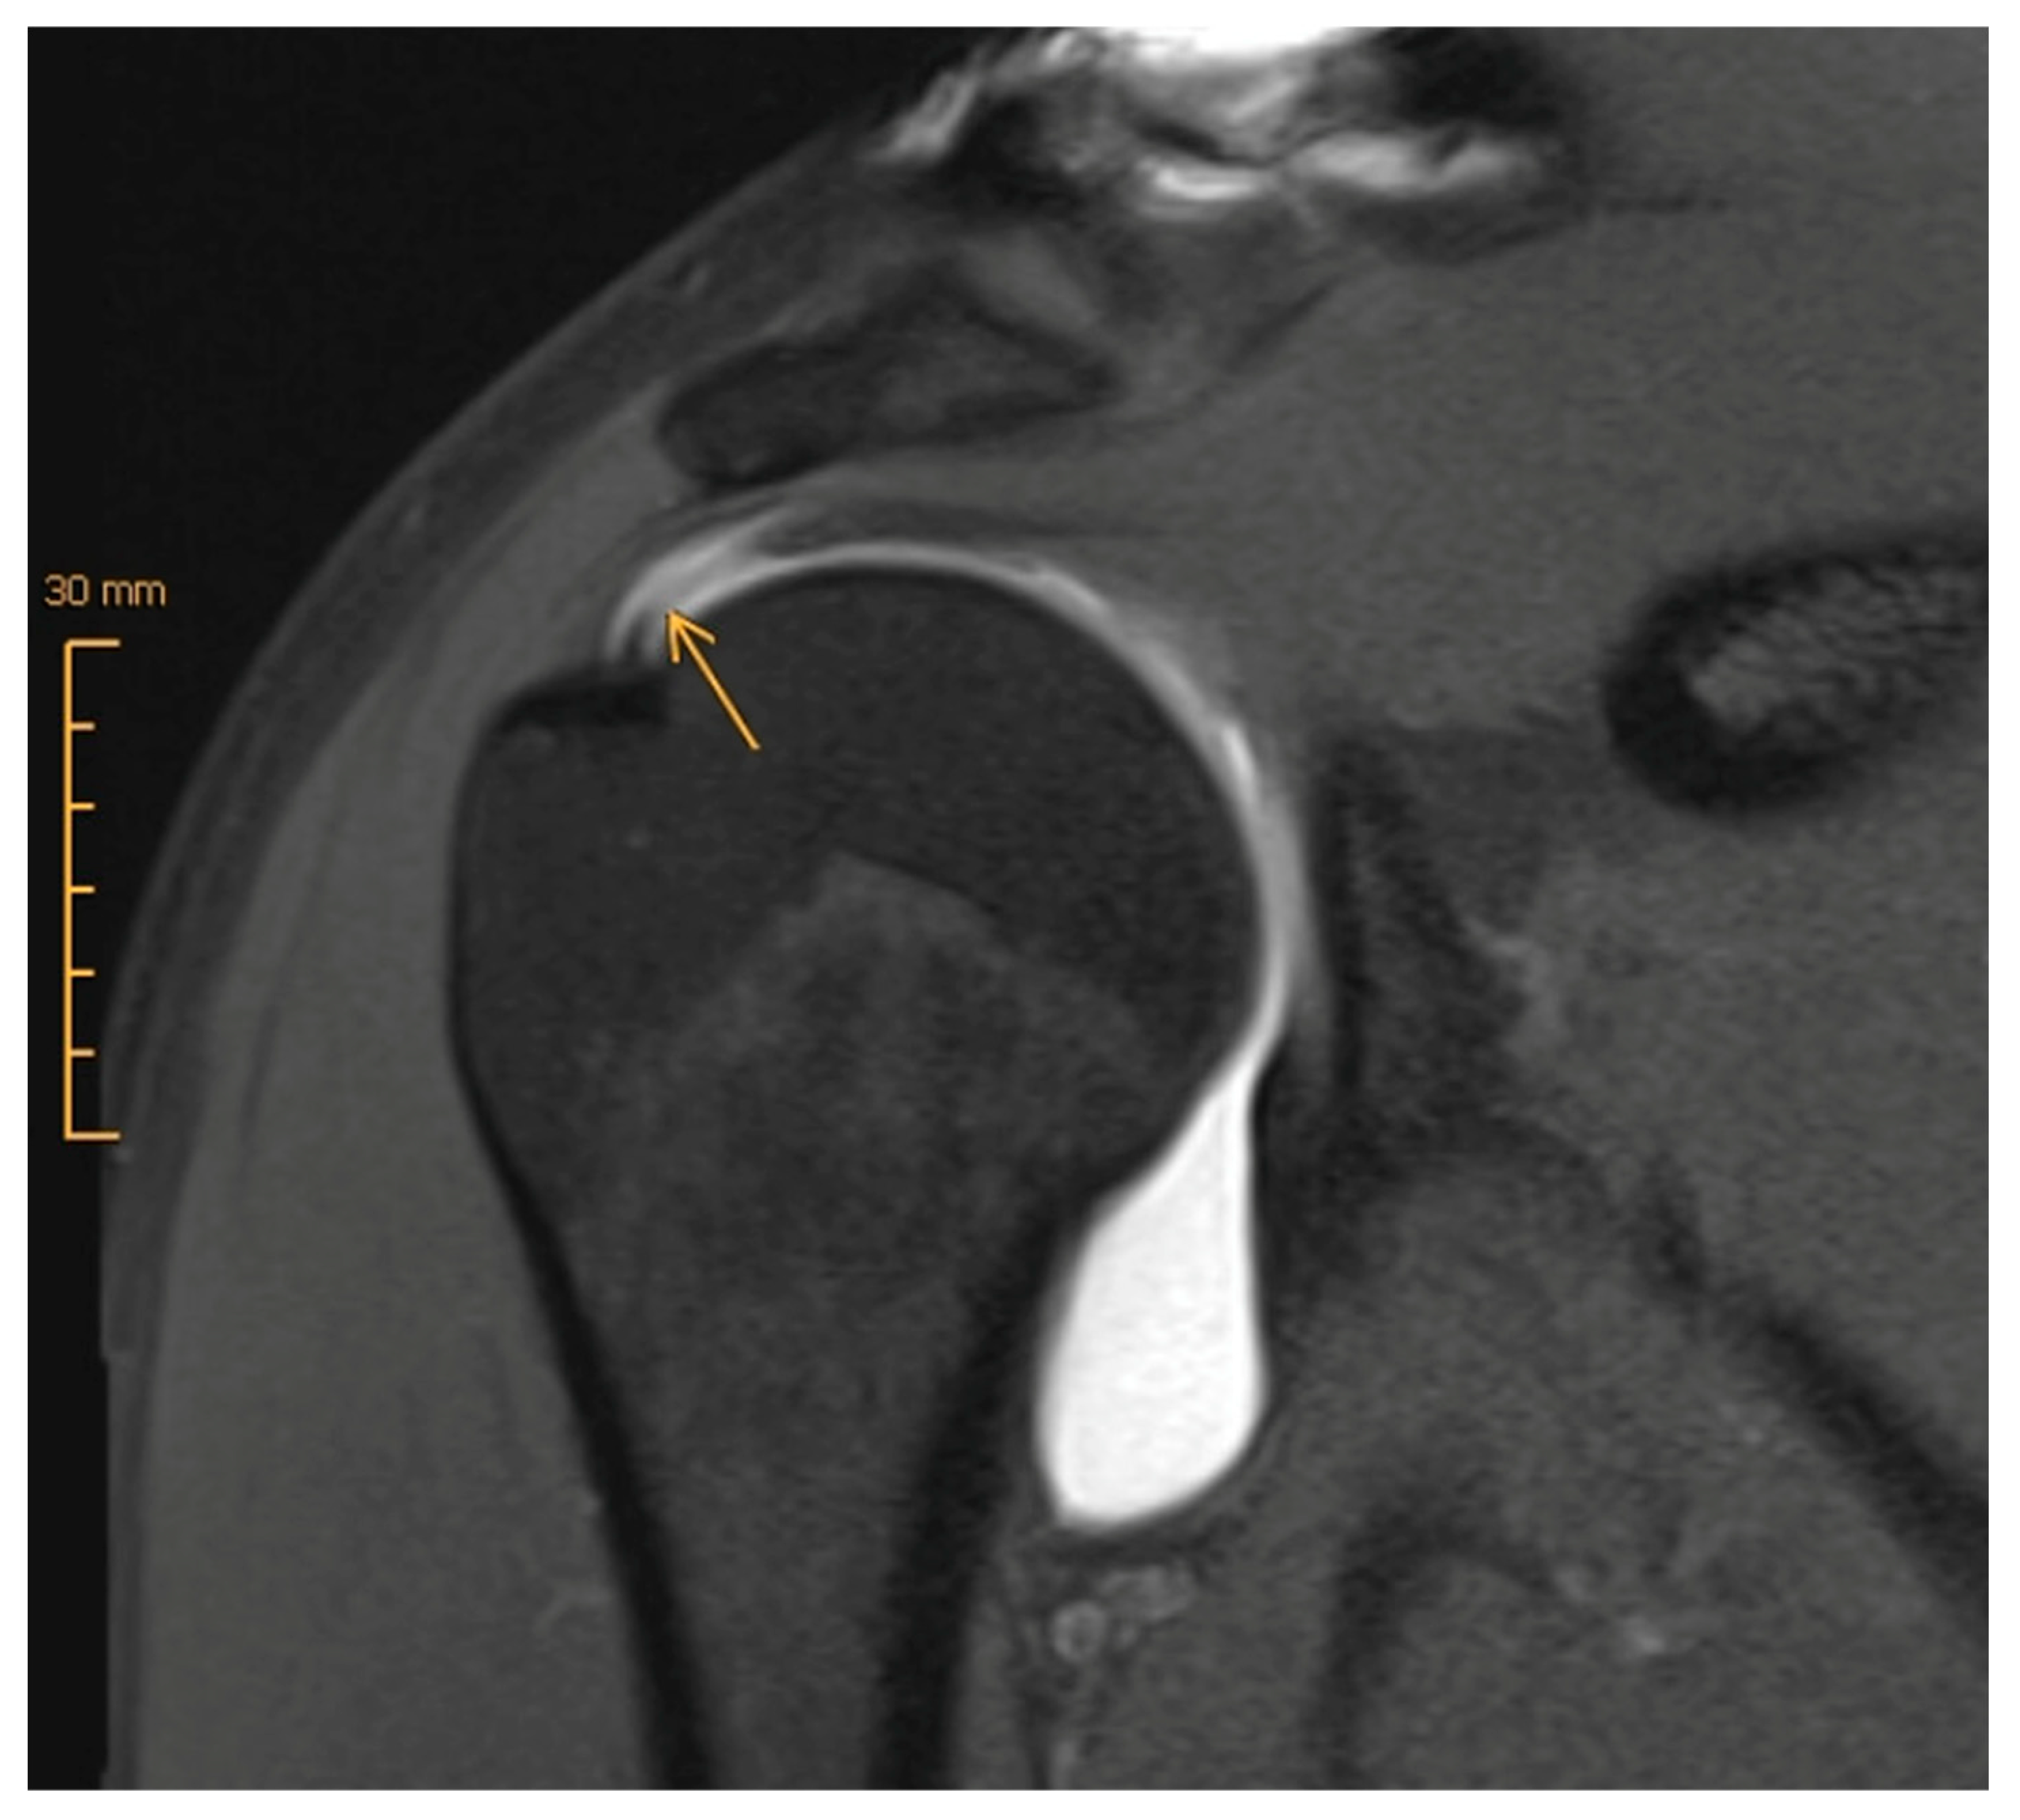

- Gottsegen, C.J.; Merkle, A.N.; Bencardino, J.T.; Gyftopoulos, S. Advanced MRI Techniques of the Shoulder Joint: Current Applications in Clinical Practice. Am. J. Roentgenol. 2017, 209, 544–551. [Google Scholar] [CrossRef]

- Honda, H.; Morihara, T.; Arai, Y.; Horii, M.; Ito, H.; Furukawa, R.; Kida, Y.; Sukenari, T.; Ikoma, K.; Oda, R.; et al. Clinical application of radial magnetic resonance imaging for evaluation of rotator cuff tear. Orthop. Traumatol. Surg. Res. 2015, 101, 715–719. [Google Scholar] [CrossRef] [PubMed]

- Shibayama, Y.; Hirose, T.; Sugi, A.; Mizushima, E.; Watanabe, Y.; Tomii, R.; Iba, K.; Yamashita, T. Diagnostic accuracy of magnetic resonance imaging for partial tears of the long head of the biceps tendon in patients with rotator cuff tears. JSES Int. 2022, 6, 638–642. [Google Scholar] [CrossRef]